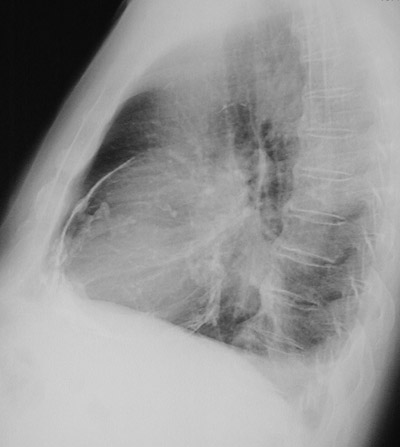

| The chest CT scan above shows a more advanced constrictive pericarditis with extensive bright calcification around the heart. In the lateral chest radiograph below, the calcification is best seen anteriorly. Such restriction of cardiac wall motion can produce heart failure. |